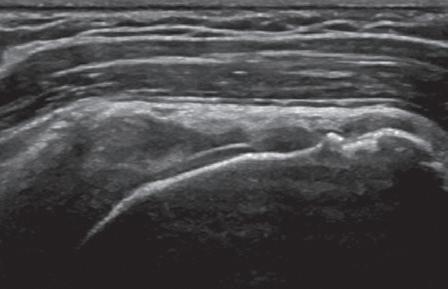

such artifact is anisotropy 6 When a tendon is imaged perpendicular to the ultrasound beam, the characteristic hyperechoic fibrillar appearance is displayed. However, when the ultrasound beam is angled as little as 2 to 3 degrees relative to the long axis of such a structure, the normal hyperechoic appearance is lost; the tendon becomes more hypoechoic with increased insonation angle (Figs. 1.10 to 1.13). A tissue is anisotropic if its properties change when measured from different directions. This variation of ultrasound interaction with fibrillar tissues involves tendons and ligaments and, to a lesser extent, muscle. Because abnormal tendons and ligaments may also appear hypoechoic, it is important to focus on that segment of tendon or ligament that is perpendicular to the ultrasound beam, to exclude anisotropy. With a curved structure, such as the distal aspect of the supraspinatus tendon, the transducer is continually repositioned or angled to exclude anisotropy as the cause of a hypoechoic tendon segment (Fig. 1.11 and Video 1.3). Anisotropy is noted both in long axis and short axis of ligaments and tendons (Video 1.4), but it occurs when the sound beam is angled relative to the long axis of a structure (Fig. 1.12). Therefore, to correct for anisotropy, the transducer is angled along the long axis of the imaged tendon or ligament; when imaging a tendon in long axis, the transducer is angled as a heel-toe maneuver (see Fig. 1.3A and Video 1.5), whereas in short axis, the transducer is toggled (see Fig. 1.3B and Video 1.6). Anisotropy can be used to one’s advantage in identification of a hyperechoic tendon or ligament in close proximity to hyperechoic soft tissues, such as

in the ankle and wrist. When imaging a tendon in short axis, toggling the transducer will cause the tendon to become hypoechoic, thus allowing its distinction from the adjacent hyperechoic fat that does not demonstrate anisotropy (Fig. 1.12). Once the tendon is identified, anisotropy must be corrected to exclude pathology. Anisotropy is also helpful in identification of some ligaments, such as in the ankle, because they are often adjacent to hyperechoic fat (Fig. 1.13). In addition, hyperechoic tendon calcifications can be made more conspicuous when they are surrounded by hypoechoic tendon from anisotropy with angulation of the transducer (see Fig. 3.63). When performing an interventional procedure, it is anisotropy that causes the needle to become less conspicuous when the needle is not perpendicular to the sound beam (see Fig. 9.8).

FIGURE 1.13 Anisotropy. Ultrasound images of anterior talofibular ligament in long axis (arrowheads) in the ankle show normal ligament hyperechogenicity (A) and hypoechoic anisotropy (open arrows) (B), when angling the transducer along the long axis of the ligament, thus aiding in identification of ligament relative to surrounding hyperechoic fat. F, Fibula; T, talus.